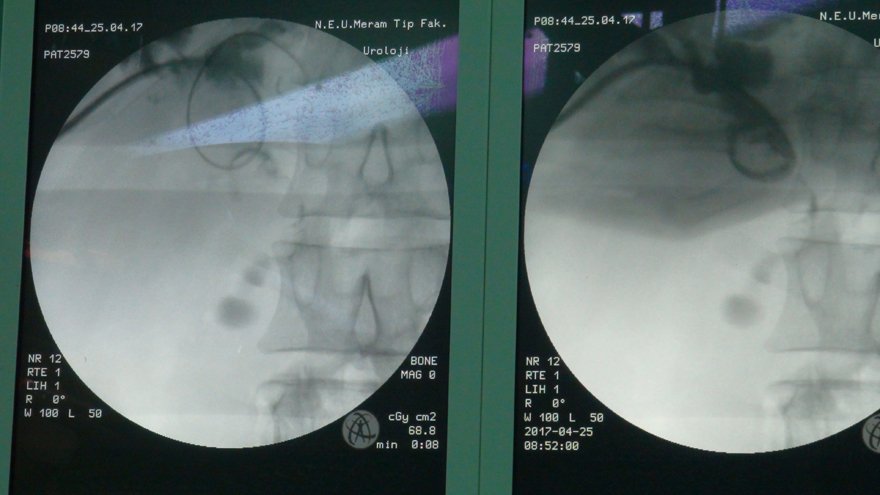

Endoskopik yöntemle karaciğer içerisindeki safra kanalına girerek taşların parçalandığını, bir kısmının dışarıya ve bağırsağa itilerek müdahalenin tamamlandığını anlatan Öztürk, şöyle devam etti:

"Karaciğer çok kanamalı bir organ. Kanallar küçük. Buradaki işlemler tahribata neden olabilir. Bizim kullandığımız aletlerle kanallarda rahat hareket edip, taşa ulaştık. Kanama ihtimalini en az düzeye indirdik. Ameliyattan sonra açılan delik daha çabuk kapandı. 'Ultra mini' diyebileceğimiz yaklaşık 2,6 (8F) milimetrelik aletleri kullanarak müdahaleyi yaptık. Yurt dışında daha kalın, yaklaşık 1 santimetreye yakın aletlerle yapılmış ender uygulamalar var. Biz ultra mini dediğimiz aletlerle bu işi dünyada ilk yapan klinik olmanın gururunu yaşıyoruz. Şu anda ameliyat görüntülerini hazırlıyoruz. Uluslararası camiaya bunu duyuracağız. Video sunumlarla uluslararası toplantılarda uygulamayı anlatacağız. Endoskopik taş tedavisi tecrübemizi karaciğerdeki taşa uyguladık. Sonuçta hastamızın da bizim de yüzümüz güldü. Hepimiz mutluyuz."